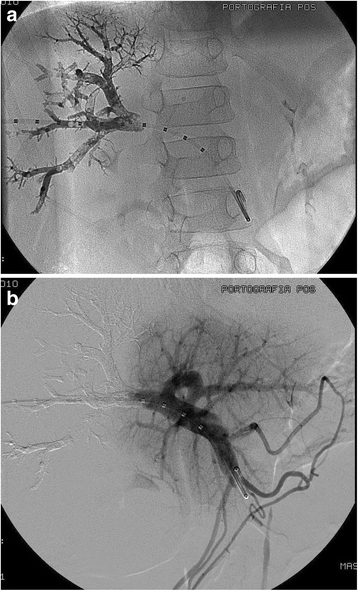

Which is the most typical first-line approach to TIPS?

R hepatic vein –> R portal vein

schedule for TIPS patency

1 month, every 3 months, then every 6-12 months

type of stent used in TIPS

Viatorr stent

it is both covered and uncovered